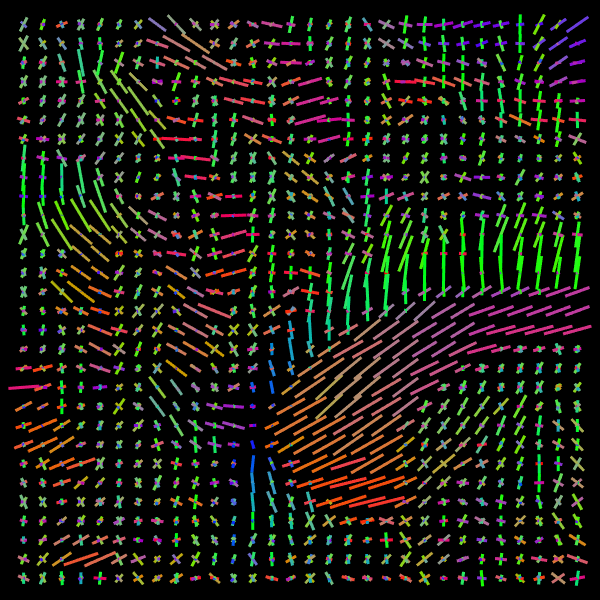

Appendix C Axonal structure estimated in real data

Refer to caption

(a) DW-MRI

(b) Slice Zoom

(c) NNLS

(d) CSD

(e) VOX

(f) NBH

Figure 13: Example 2. Predicted intravoxel structure in real data.